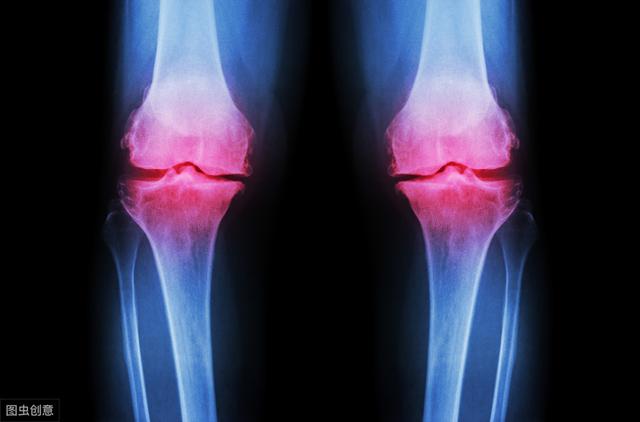

2,适合膝关节流动也是治疗退行性骨关节炎的自身申请。关节炎不单导致关节疼痛,也使关节僵直。运动可无效减缓枢纽关头生硬,维持关节锐敏性,同时,训练枢纽关头左近肌肉、缓解因疾病导致的肢体肌肉萎缩,这些最终会减少骨关节炎患者因枢纽关头有力或不搭腔所致的关节几回再三损伤和退变加重。

3,虽然,骨关节炎的运动训练需要有专业医护、康复职员领导,熬炼门径和程度要合理,预防关节软骨遭受过火应力、枢纽关头炎症减轻和激起关节疼痛。

2,真实,早期骨枢纽关头炎所形成的关节疼痛与早期骨关节炎所形成痛苦悲伤有很大辨别,早期主假定软骨磨损利诱关节滑膜炎和软骨下骨水肿所惹起的疼痛,这种针对软骨磨屑的滑膜炎与水肿相对较轻,一样平常消炎止痛药均有用。

3,但到了晚期,软骨已磨完,勾当时会进一步抵触软骨下方的骨机关,骨内含有大量无机盐,如焦磷酸钙,这些晶体源源不时的监管到枢纽关头腔,可诱发猛烈的滑膜炎症,临床称之为“假性痛风”,此时,单用消炎止痛药已难以收效。同时,关节生硬、关节囊疤痕纤维化也加剧了关节活动时的疼痛。